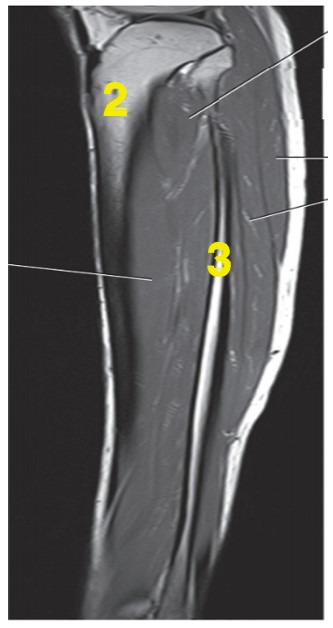

Number 2 is on the __________ side of the patient.

lateral

What anatomy is # 3?

fibula